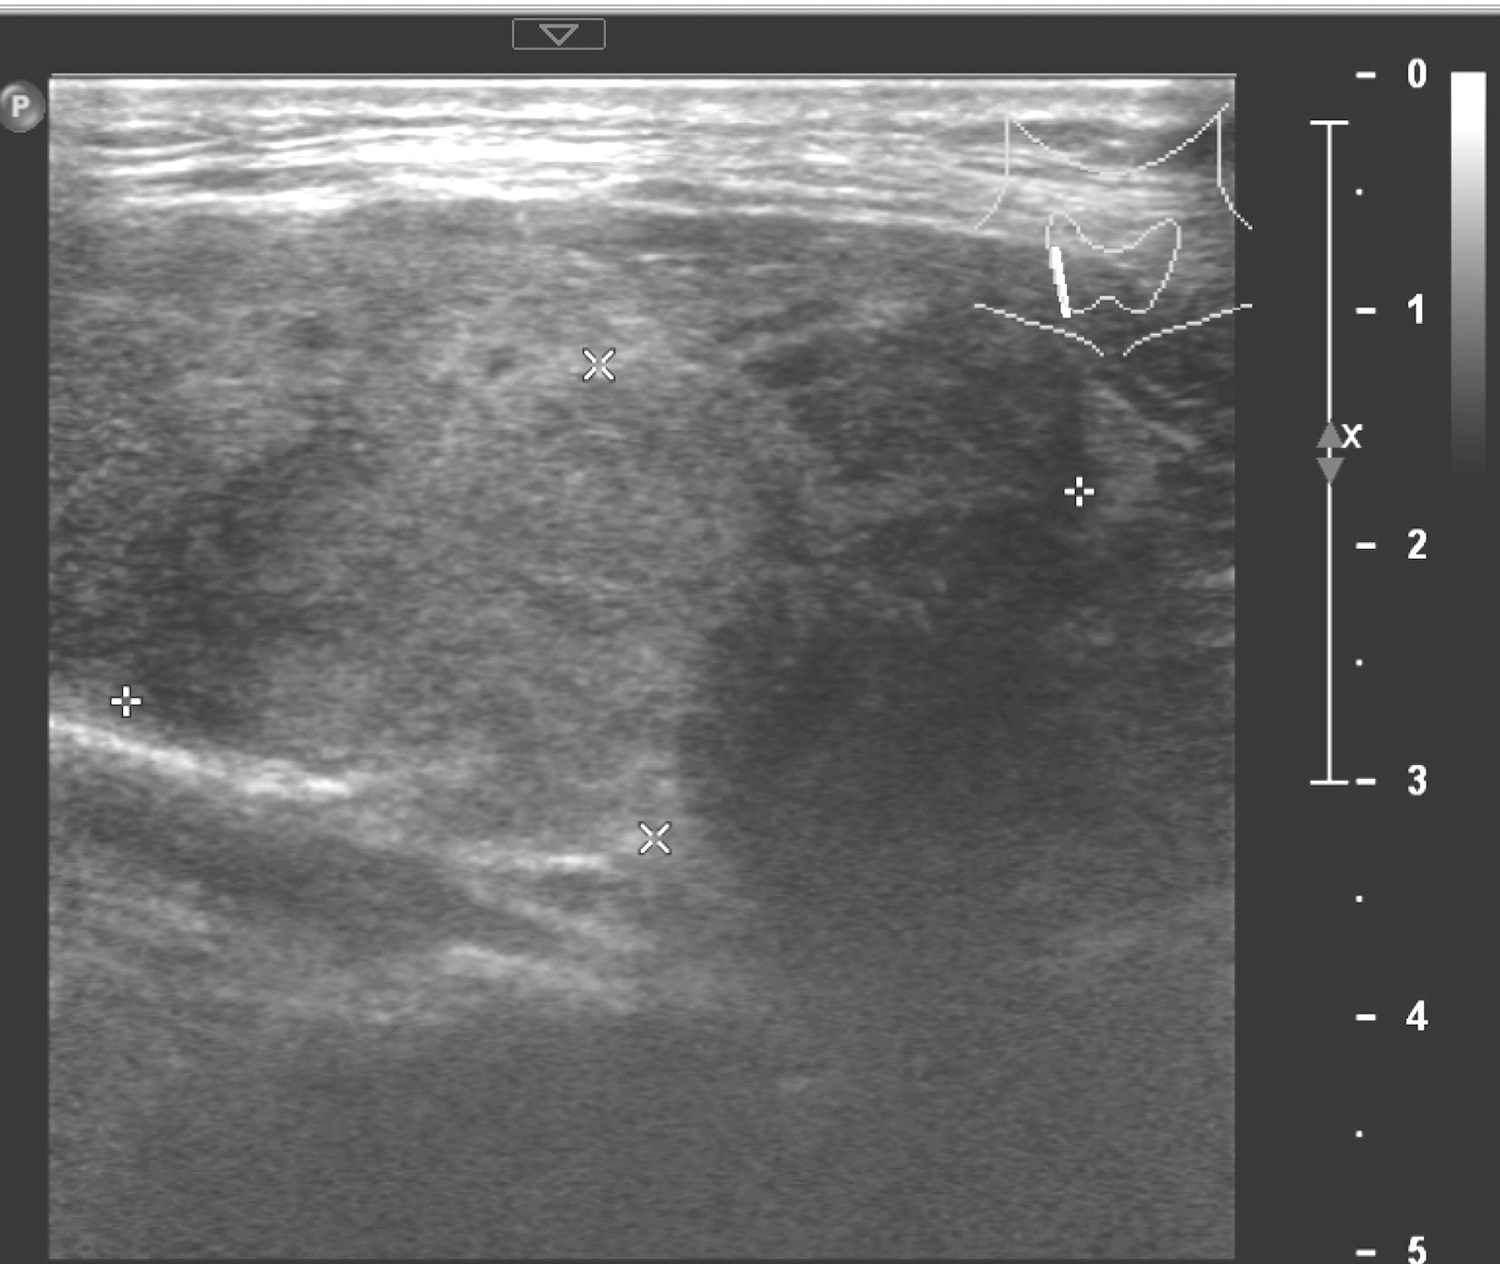

1.2017年5月12日颈部超声

甲状腺右叶肿物,大小约4.2cm×2.0cm,边界欠清楚,形态不规则,CDFI可见血流信号(图1、图2)。左叶低回声结节,大小约0.3cm。右侧气管旁,中下颈及锁骨上多个低回声结节,较大者约1.1cm×0.6cm。余双颈未见肿大淋巴结。

图1 颈部超声示甲状腺右叶肿物

甲状腺右叶肿物,考虑恶性;甲状腺左叶结节,考虑良性;右颈淋巴结探及。